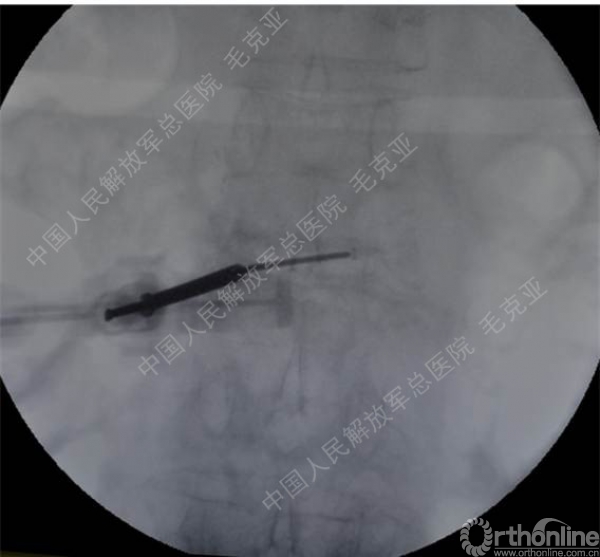

导语:随着社会老龄化的不断加速,骨质疏松性椎体压缩骨折作为一种普遍存在的老年骨科疾病已经成为现今骨科界的一个热点话题。传统的保守疗法治疗效果不佳,而现有的椎体增强技术又具有多种风险和缺陷。针对这种现状,中国人民解放军总医院毛克亚教授提供了一种新的解决方法。